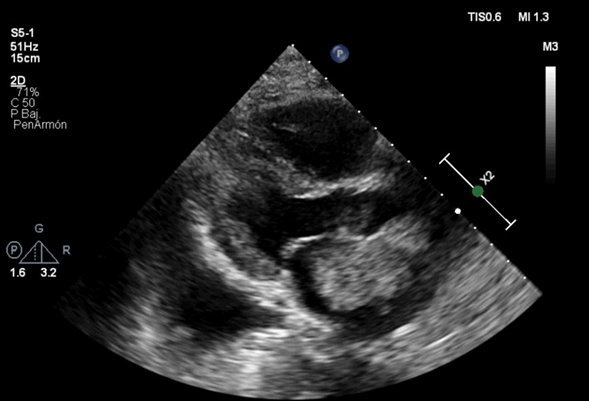

Bajo el contexto clínico y de acuerdo a los paraclínicos tomados fuera del Hospital Universitario se sospechó inicialmente un síndrome coronario agudo sin elevación del segmento ST, con un electrocardiograma no diagnóstico y sin incremento en el nivel del biomarcador. Posterior a esto se orientó el caso como un edema pulmonar cardiogénico, para el cual se solicitó un Eco TT en cuyo reporte se describió la presencia de un mixoma que protruye a través de la válvula mitral, Fracción de Eyección del Ventrículo Izquierdo (FEVI) del 55% y un cálculo indirecto tomado con la ecuación de Bernoulli modificada de presión sistólica de la arteria pulmonar (PSAP) de 110 mmHg (Figura 3).

Figura 3: Ecocardiograma transtorácico. Referencias: VD- ventrículo derecho VI- ventrículo izquierdo AI-aurícula izquierda. La flecha señala una masa gigante adherida al septum interauricular que protruye a través de la válvula mitral compatible con Mixoma auricular con área de 11 cm2.

El método más usado para el diagnóstico de mixomas auriculares es el EcoTT, pero si el resultado no es óptimo puede utilizarse el EcoTE 5. La sensibilidad del EcoTT para el diagnóstico de los mixomas es cercana al 95% y la del EcoTE es del 100% 5, siendo esta la prueba de mayor rendimiento en la detección del sitio de inserción, permitiendo la visualización de trombos, masas y otros elementos dentro de las cámaras cardiacas, aparte de estimar el tamaño 33.

En este caso puntual el ecocardiograma fue de utilidad tanto para el diagnóstico del mixoma auricular como para el de hipertensión pulmonar, ya que es una modalidad útil y no invasiva inicial que permite establecer la probabilidad de esta con una sensibilidad del 83% y una especificidad del 72% 34. Aunque el ecocardiograma no provee información sobre la caracterización del tejido y no diferencia entre masas malignas y benignas, la RNM puede proveer una excelente caracterización de los tumores cardiacos, sin embargo, cabe resaltar que tres cuartos de estas son benignas y el 50% de las benignas son mixomas, por lo tanto, son la masa cardíaca más prevalente, sin embargo la confirmación diagnóstica requiere estudio histológico 29.